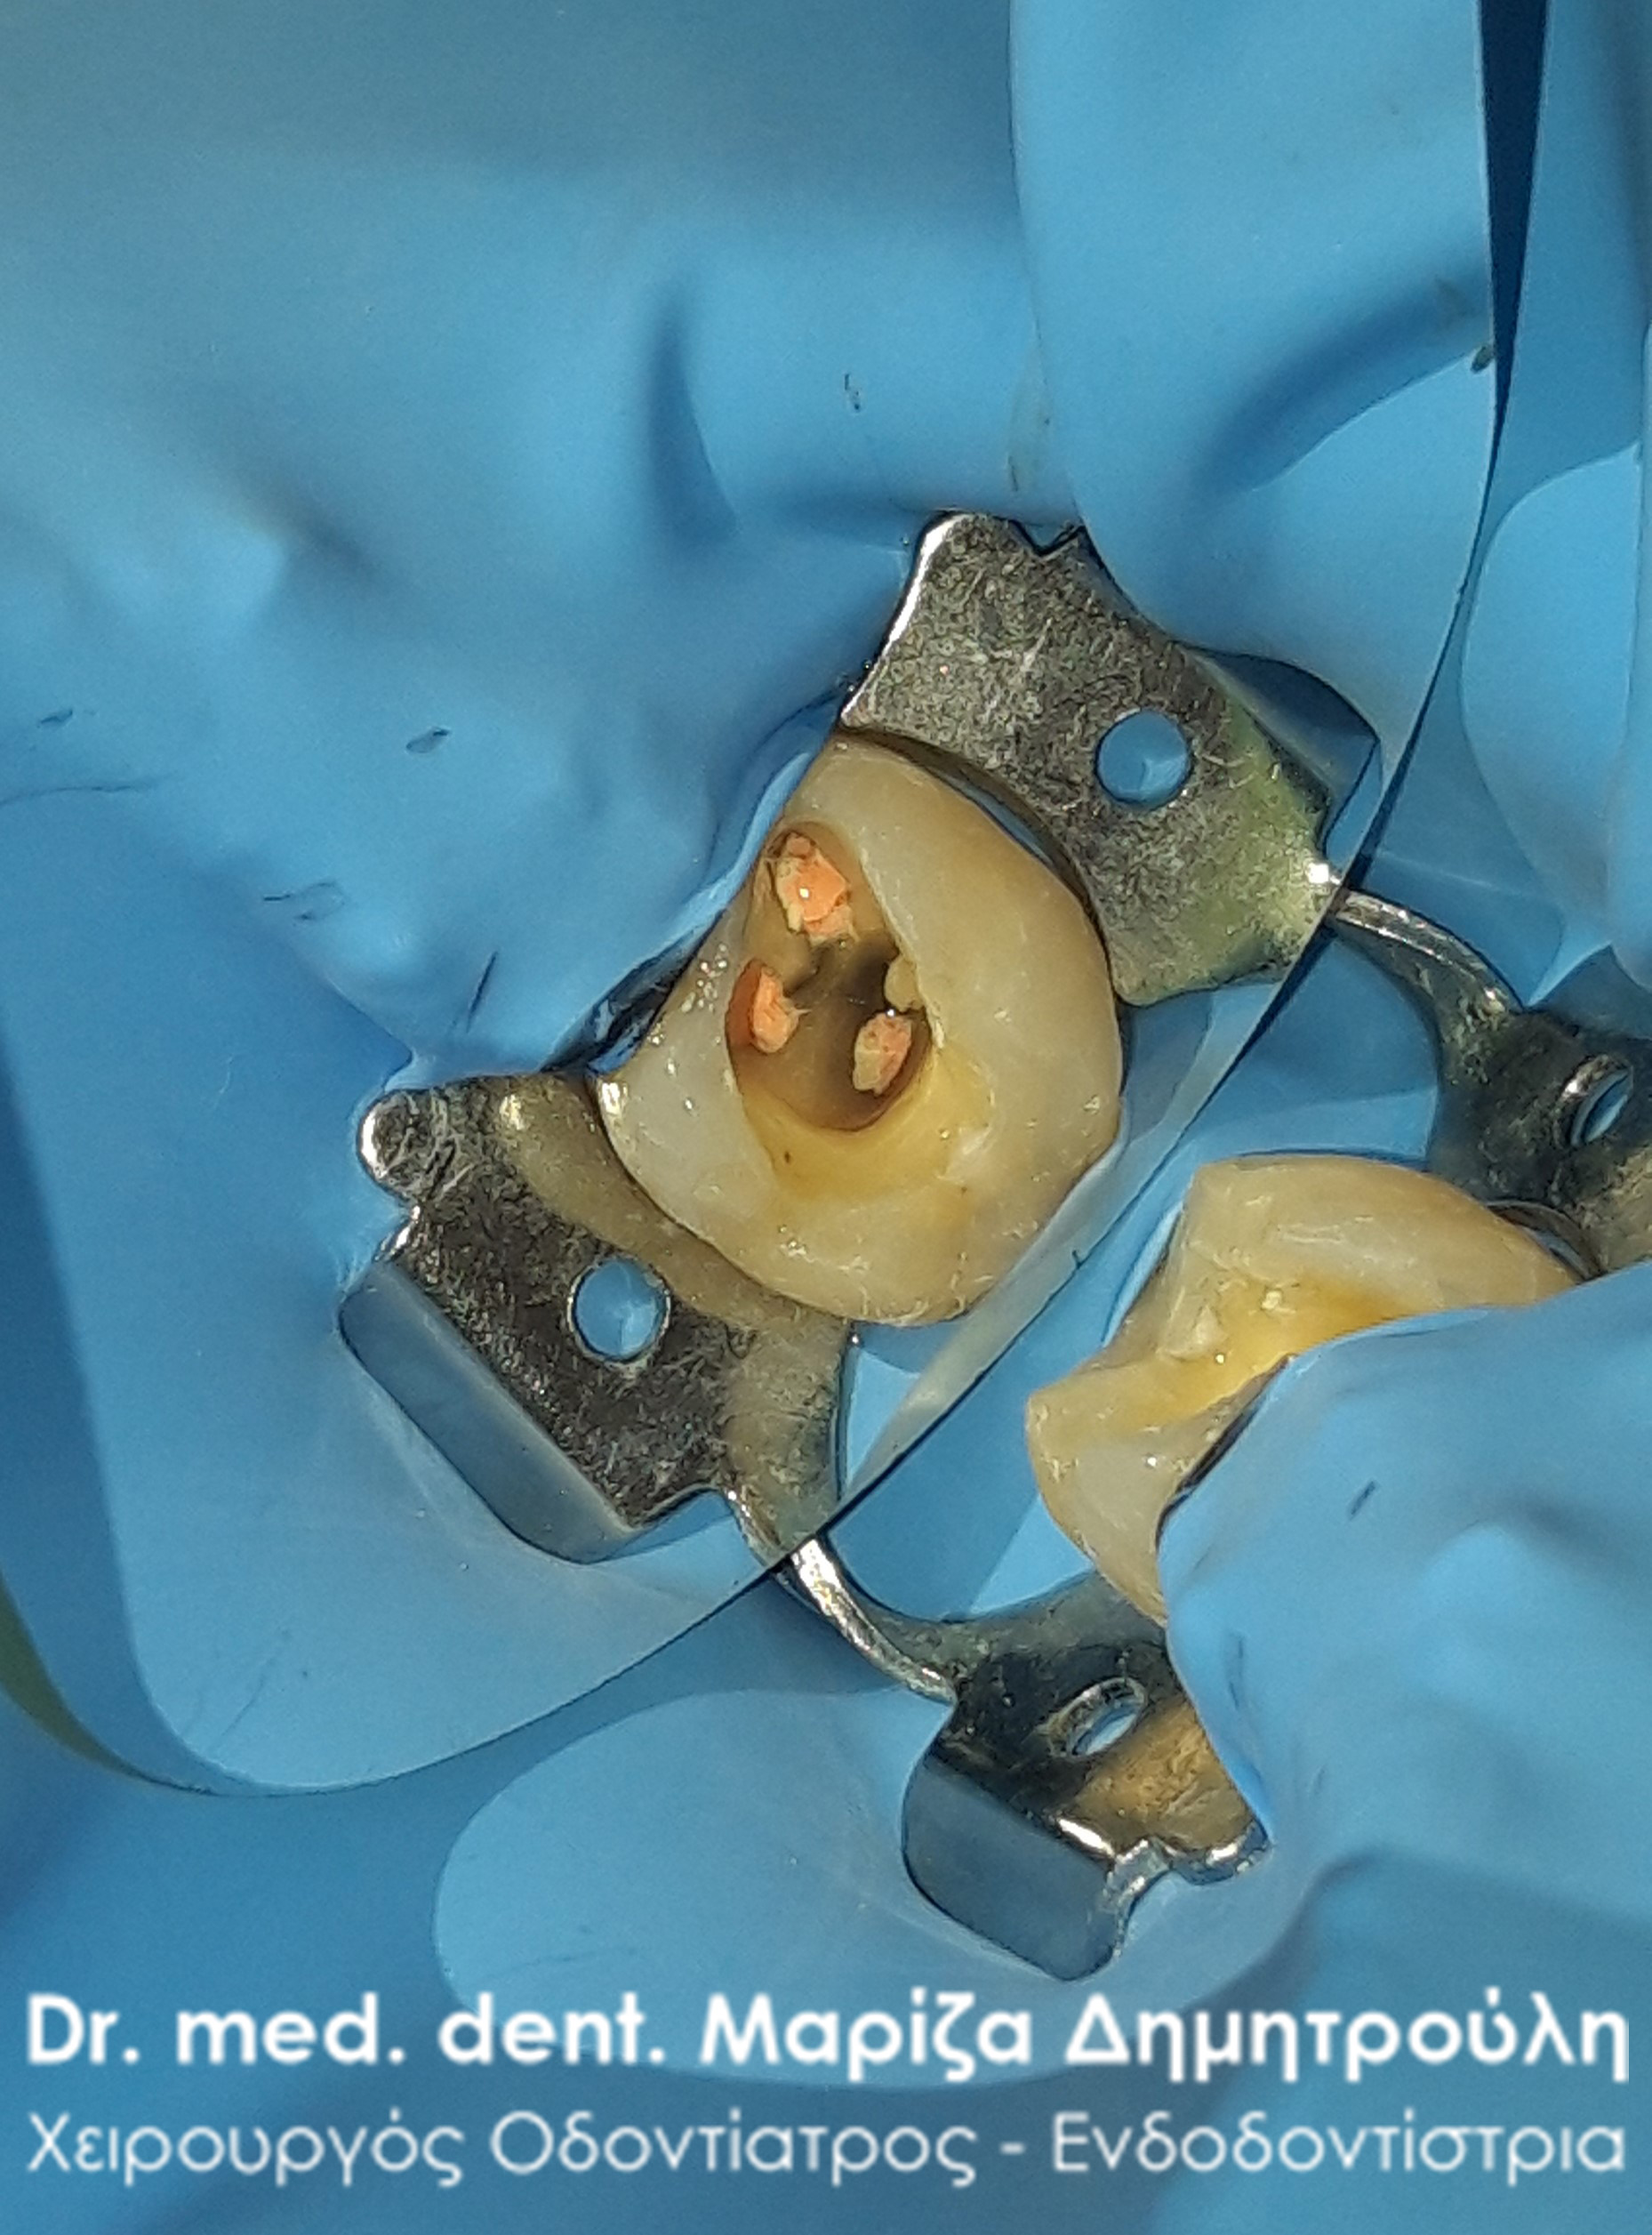

Pus after opening the tooth

Clinical photo of root canal filling

Final photo of the tooth after the root canal treatment